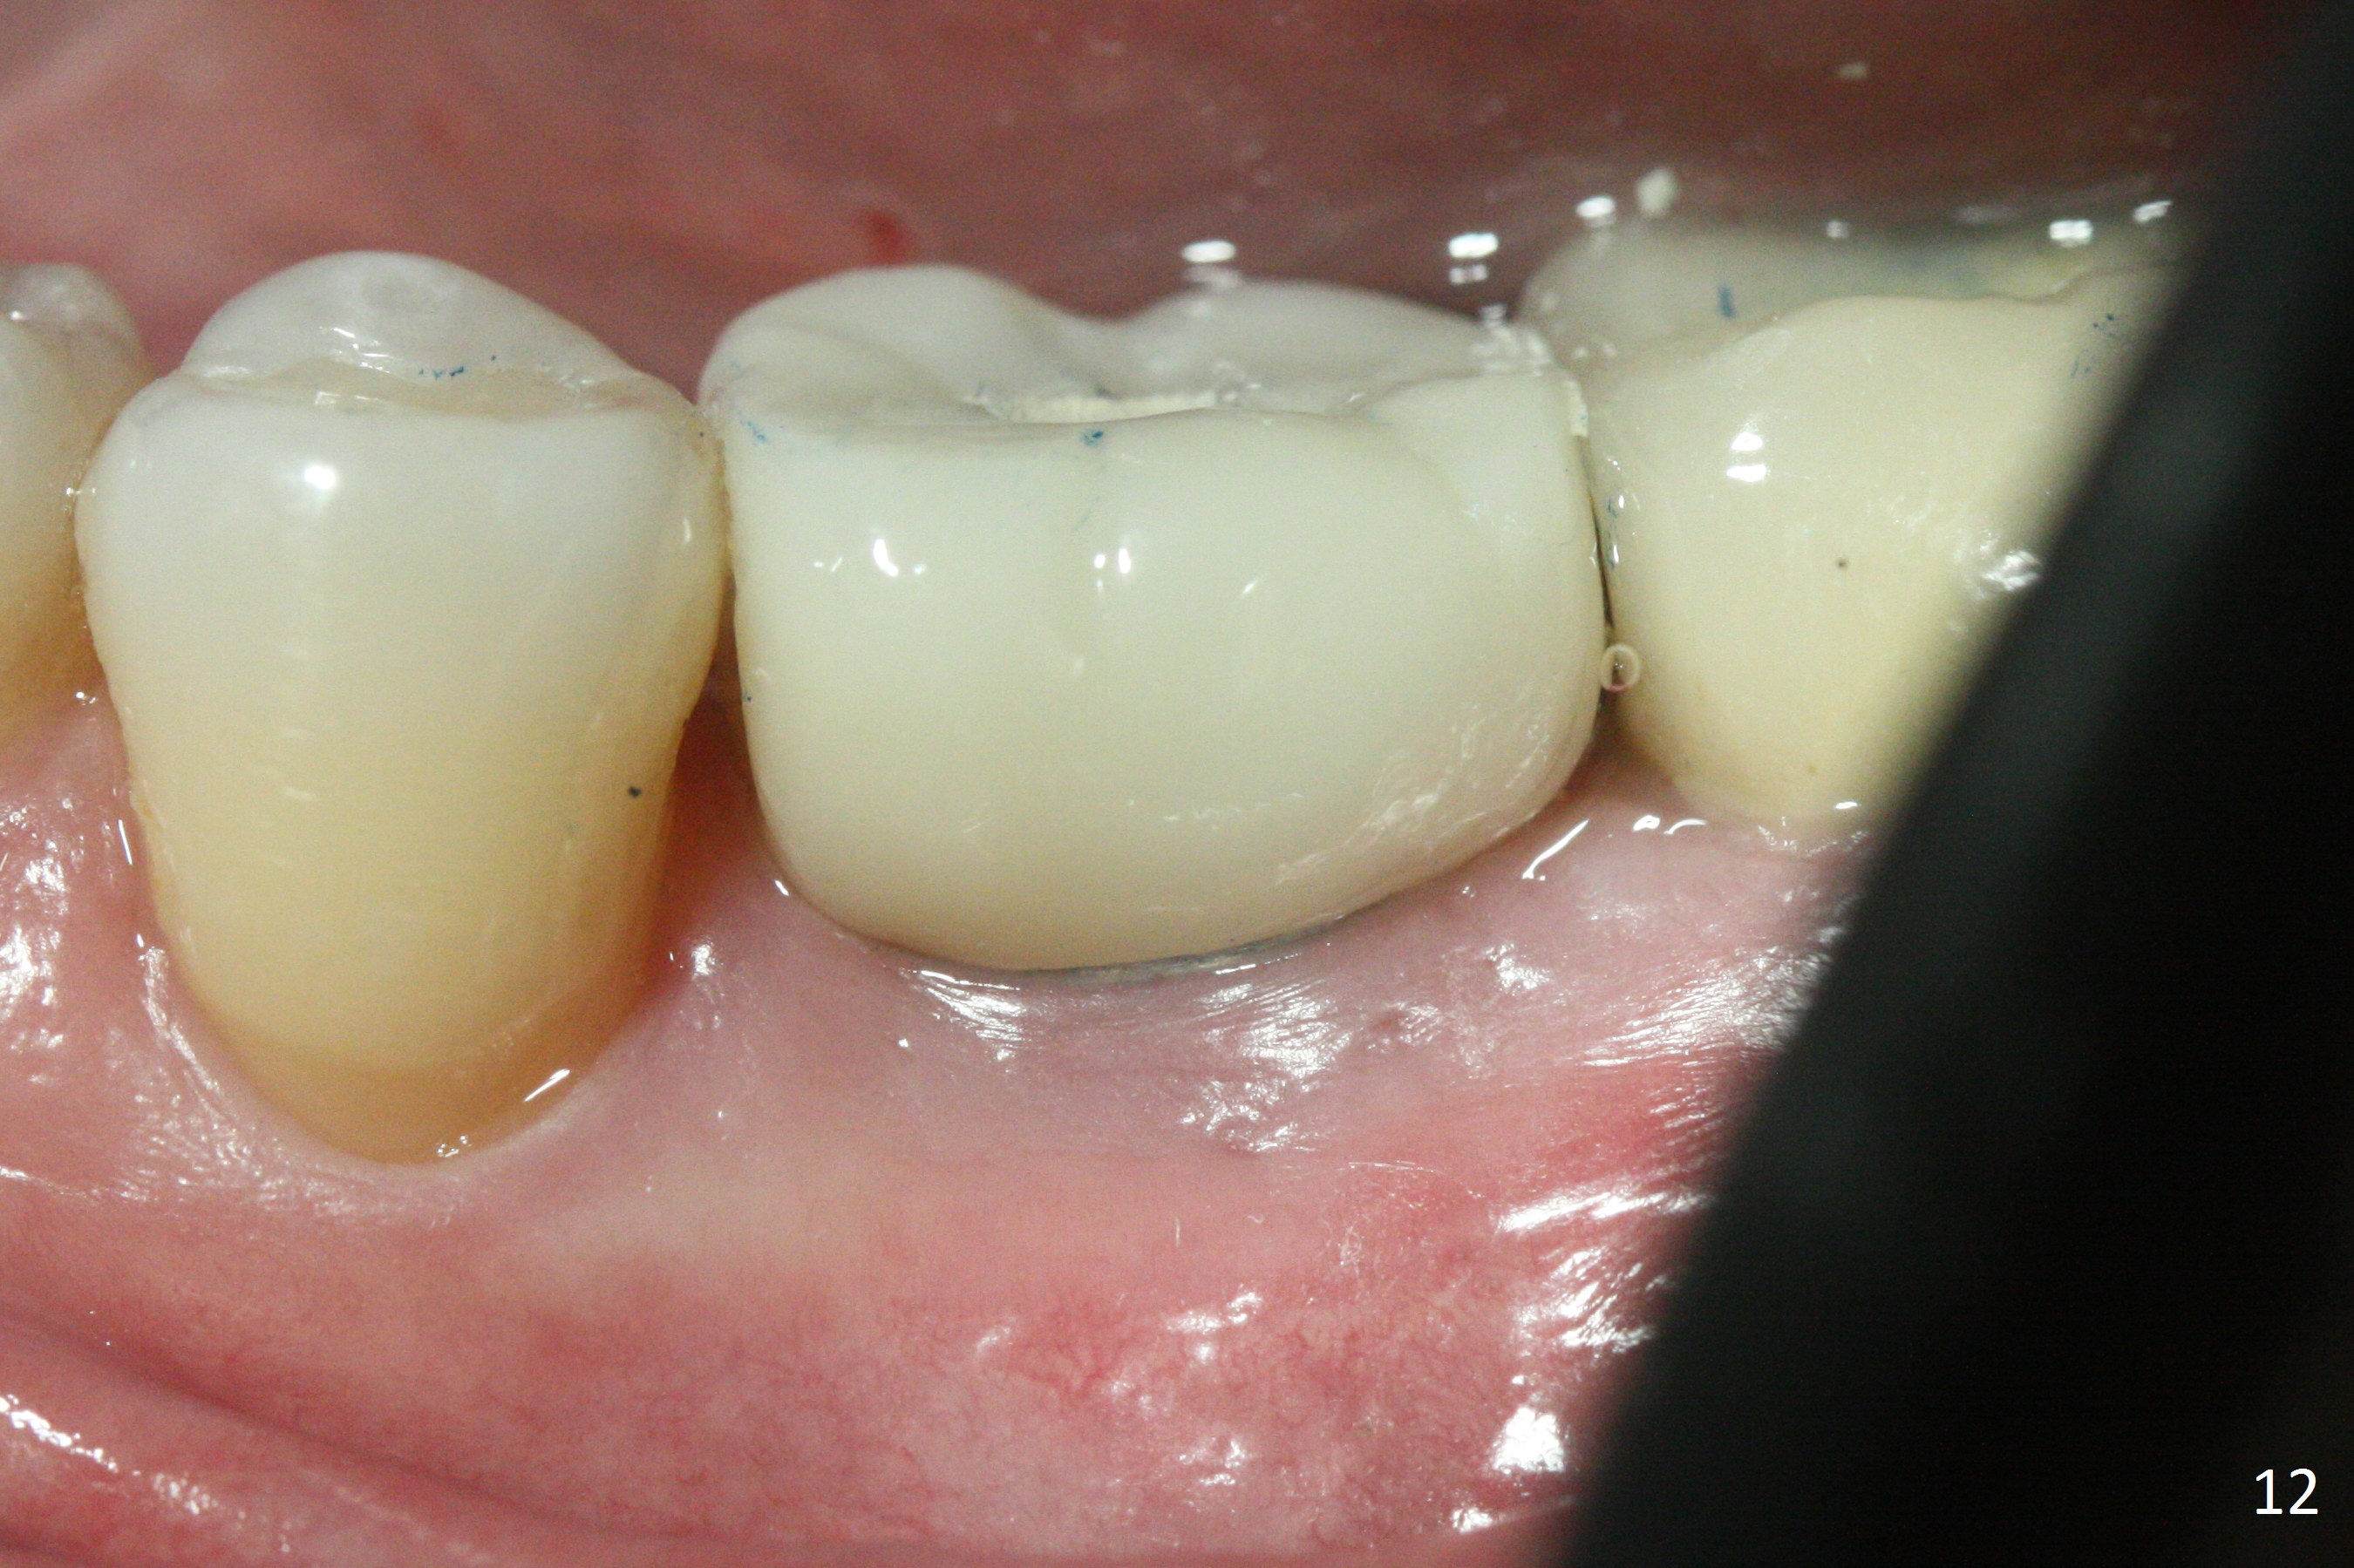

The gingiva looks healthy 8 months postop (3 months post cementation (after abutment screw retightening and addition of porcelain to proximal surfaces, Fig.12).  New bone has apparently covered the implant plateau (Fig.13 arrows). Bone density between threads increases 9 months post cementation (Fig.14).  There is 2 mm bone superior to the implant plateau mesial and distal 1 year 9 months post cementation (Fig.15,16).  The crown/abutment is loose 3 times (3 months (Fig.14), 11 months (between Fig.14 and 15) and 2 years 3 months post cementation).  In spite of being stable 3 years 10 months post cementation, a smaller abutment is placed (Fig.17 (PA), 18 (BW)) with impression for a new crown.  After intraoral cementation, the new crown/abutment is removed for residual cement removal.  When the complex is reseated, it is not smooth, probably due to proximal undercut.  Fortunately the abutment appears to be completely seated, followed by 20 Ncm torque (Fig.19).